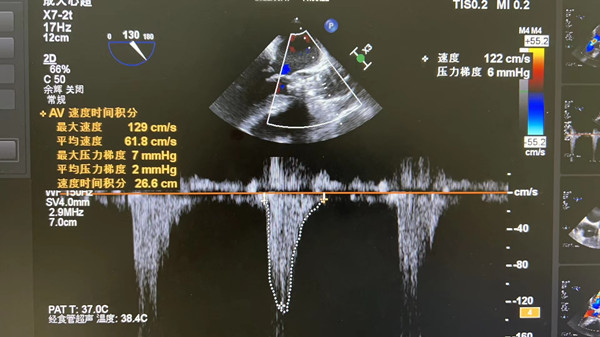

在我院心外科裴斐主任医师,麻醉科刘鹏斌主任医师、罗斌主治医师,超声科韩东刚副主任医师、金鑫主治医师,曹春晖护士长领导的护理团队等多学科协助下,韩振华主任、王新宏副主任医师、刘小军主治医师等先为患者行冠脉造影提示右冠近段95%狭窄(图1),先行PCI干预,右冠植入3.0x22mm支架1枚(图2)。后成功为患者植入TAV24mm VitaFlow瓣膜系统,DSA造影显示主动脉瓣位置良好,未见明显瓣周漏(图3),左右冠脉造影正常,术后即刻心脏超声示最大跨瓣流速129cm/s,最大跨瓣压差7mmHg(图4),顺利结束手术。

图4